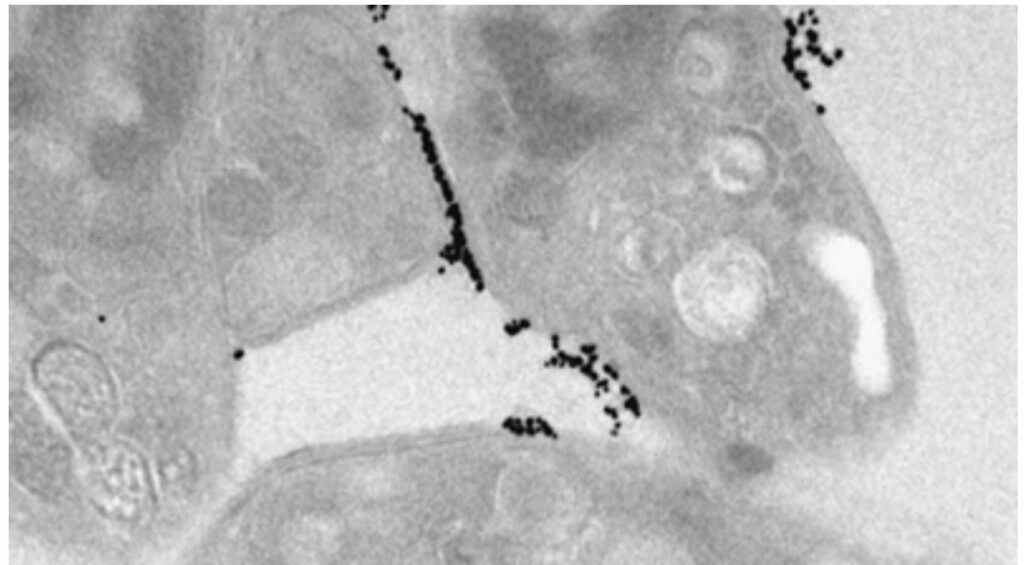

“The beautiful thing about [nano gold] is that we can other molecules on the surface of the gold in a very controlled way.”